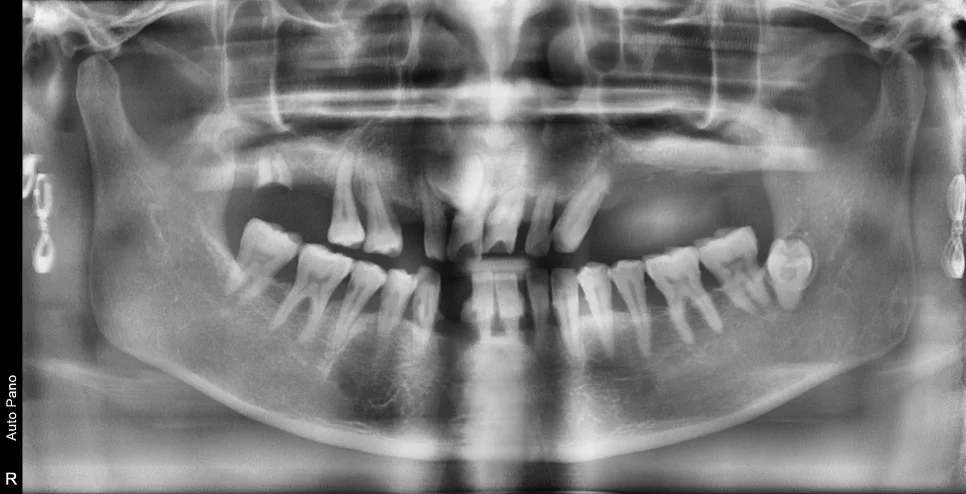

치료 전 (Before)

어금니를 조기에 상실하게 되면 상대적으로 앞니가 많은 힘을 받게 되고, 이로 인해 앞니가 버티지 못하고 흔들리게 되는 경우가 많습니다ㅜ

많은 치석과 치조골의 소실로 대부분의 치아를 발치해야 하며 임플란트 식립이 필요합니다. 보통 많은 치아의 발치 및 임플란트가 계획된 경우 위아래 두 번에 걸쳐 임플란트를 식립하게 됩니다.

수술 전후 파노라마 비교